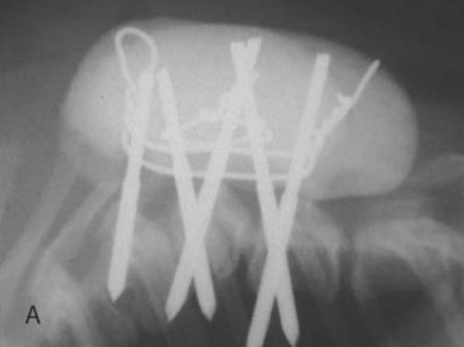

Κοιλιοραχιαίο και πλάγιο ακτινογράφημα που δείχνει τη σπονδυλοδεσία στη θωρακική μοίρα της ΣΣ σε σκύλο με ημισπόνδυλο.

Ήλοι με θετικό σπείρωμα έχουν εισαχθεί στον Θ6, Θ7 και Θ8 και έχουν συνδεθεί μεταξύ τους με PMMA σε σκύλο με ημισπόνδυλο.